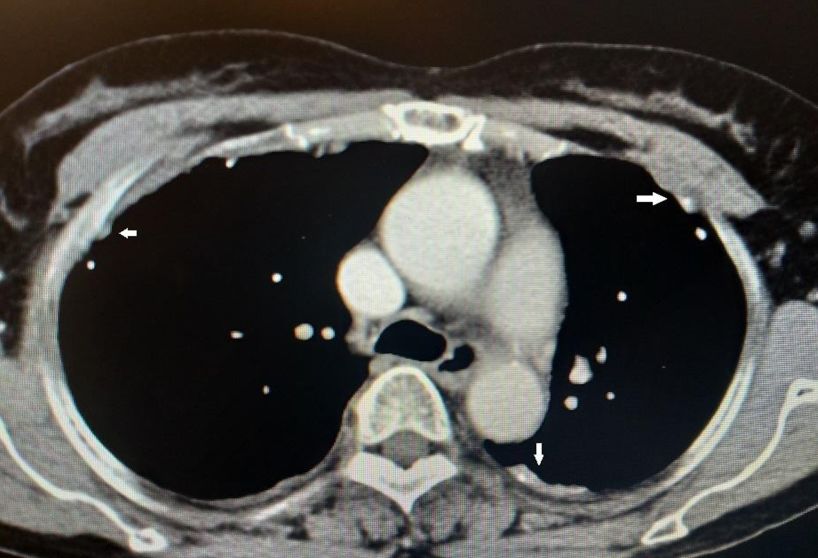

图示:患者两侧胸膜可见结节、钙化影(白箭)

到目前为止,除了胸腔积液之外,仔细阅读该患者胸部CT发现该患者的另外一个特点就是胸膜增厚、结节、钙化影。通过这一线索,不排除有胸膜来源疾病的可能。